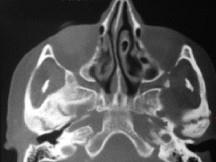

问题 关于颞下颌关节强直(如图)的描述哪项是正确的()

选项 A.颞下颌关节强直常常突然发生 B.关节及关节周围组织器质性病变造成开口困难或完全不能开口 C.颞下颌关节内强直是关节内骨性黏连 D.颞下颌关节外强直是关节外纤维黏连 E.混合性下关节强直是指关节内,外强直同时发生,又称颌间挛缩

答案 B